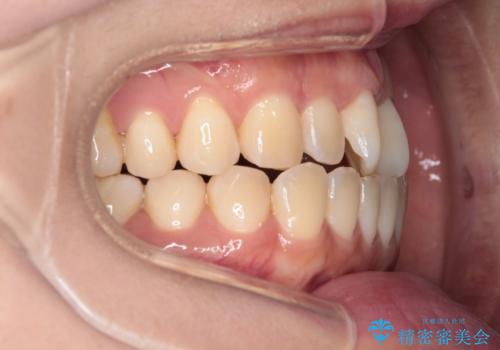

【インビザライン】前歯の捻れ気になる

- 上の前歯の捻れを主訴に来院されました。

前歯の捻れとがたつきを改善するために、IPR(歯と歯の間を削る処置)と歯列拡大をすることで歯並びを整えていく治療計画を立てました。

かみ合わせを整えるためにゴム掛けも行いながら、治療していきました。

患者様にマウスピースの使用とゴム掛けを頑張っていただいたおかげでリファイメント(マウスピースの再発注)も1回で終了することができました。